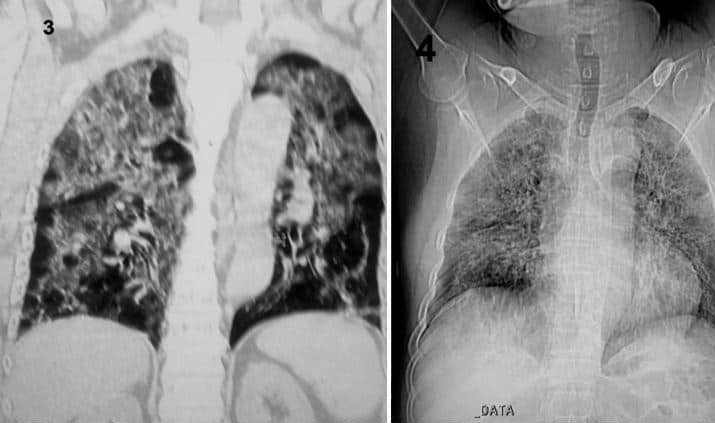

លោក​វេជ្ជបណ្ឌិត​រូប​នេះ​បន្ត​ថា មេរោគ​បម្លែង​ខ្លួន​ថ្មី​នេះ​កំពុង​វាយ​លុក​សួត​ខ្លាំងក្លា​បំផុត ដែល​យើង​ហៅ​ថា រលាក​សួត​ស្រួច​ស្រាល់។ ជំងឺ​រលាក​សួត​ស្រួចស្រាល់​ជា​ការ​រលាក​សាច់​សួត​លឿន​បំផុត​ដែល​បង្ក​ឲ្យ​មាន​ការ​ថយ​ចុះ នៃ​ការ​ប្តូរ​អុកស៊ីសែន​ក្នុង​សួត ហើយ​ឈាន​ទៅ​ដល់​កង្វះ​អុកស៊ីសែន​នៅ​ក្នុង​ឈាម និង​កង្វះ​អុកស៊ីសែន​ទៅ​ចិញ្ចឹម​សិរីរាង្គ​ផ្សេងៗ​ទៀត​ក្នុង​ខ្លួន​មនុស្ស។ ដូច្នេះ​ហើយ​ភាគ​ច្រើន​បាន​ជា​អ្នក​ជំងឺ​ឆ្លង​វីរុស​កូវីដ ១៩ អាច​ប្រឈម​នឹង​ការ​ស្លាប់​ ចំពោះ​ជំងឺ​មាន​អាយុ​ច្រើន ប្រពន្ធ័​ភាពស៊ាំ​ខ្សោយ និង​មាន​ជំងឺ​រ៉ាំរ៉ៃ​ដូច​ជា ជំងឺបេះដូង ខូច​តម្រងនោម ជំងឺ​សួតរ៉ាំរ៉ៃ​ជាដើម។